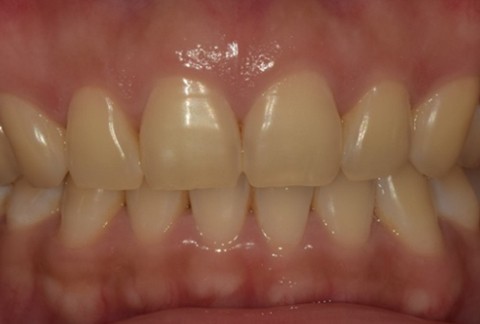

임플란트-전후사진